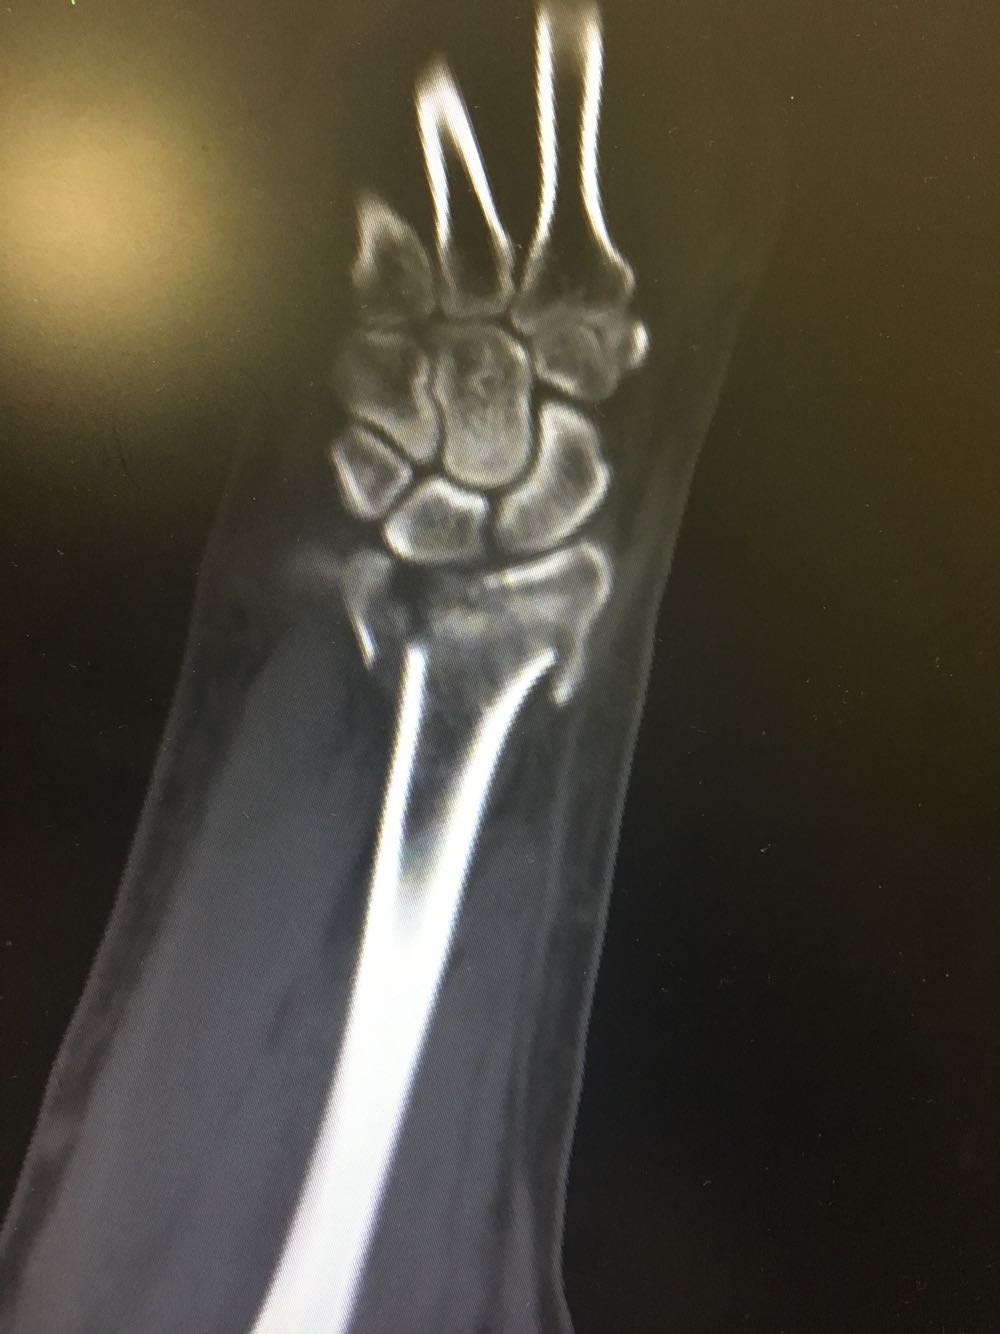

右尺桡骨双骨折

患者,男性,52岁 主诉:摔倒后右腕关节活动受限2天 现病史:患者于2天前于不慎,身体向右摔倒,右手掌着地后突感右侧腕部剧烈疼痛,后出现肿胀伴活动障碍,否认头晕头痛、恶心呕吐等不适,未见淤斑淤点,遂至我院就诊,查X片示:右侧桡骨远端及齿骨茎突骨折,现为进一步诊治收治入院,发病以来,神清,精神可,胃纳夜眠可,二便无殊,体重无明显变化。

查体:右手腕部压痛明显,伴活动受限,其余部位压痛不明显,患侧手指感觉及运动正常。 辅检:腕部CT

诊断:尺桡骨远端骨折(右侧) 治疗:完善术前检查后手术内固定